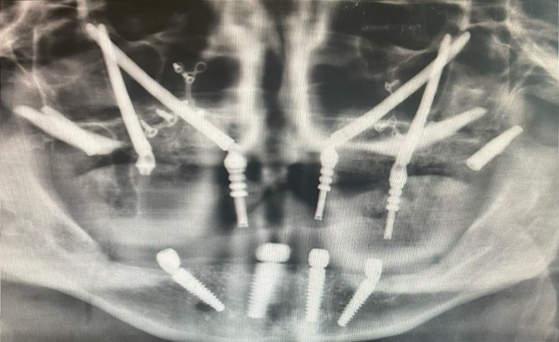

World-Class Expert Perinasal, Pterygoid, and Zygomatic Implants

Dr. Cesar Guerrero has spent 30 years renewing lives by offering specialized surgical care that improves quality of life and relieves pain. His extensive training with top doctors across six continents makes him an expert in his field. One of Dr. Guerrero’s offered services are Perinasal, Pterygoid, and Zygomatic Implants, which are advanced solutions designed for patients with severe bone loss, offering a stable, effective foundation when traditional implants are not an option.